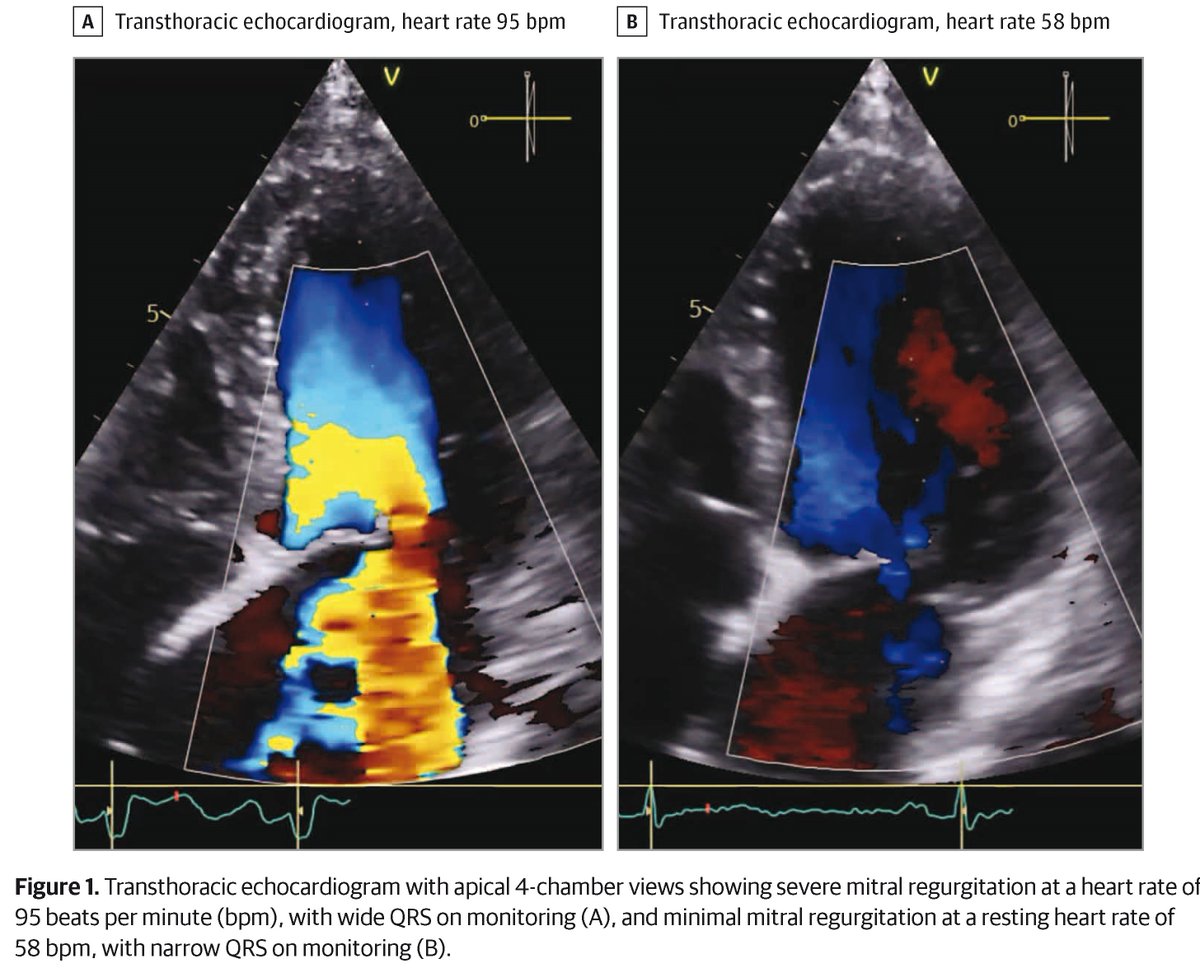

An older woman w a history of coronary artery disease presents w dyspnea upon exertion. Transthoracic echocardiogram reveals severe mitral regurgitation, and an ECG reveals sinus tachycardia w left bundle branch block. What would you do next? ja.ma/4bwXtqs Charles Guenancia